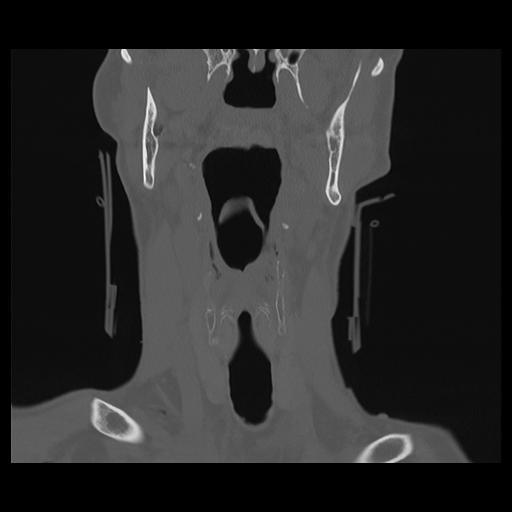

16 HUESO,,Coronal,2.000,HUESO,Coronal,